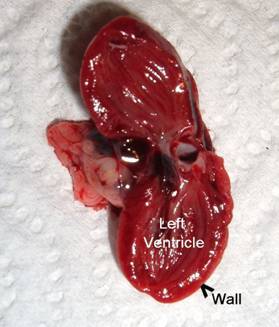

Step 9: Cut

the heart out of the chest and cut it in half longitudinally to measure the

width of the left ventricle and the thickness of its walls.

This is a normal heart showing the normal size This

heart has a mild case of hypertrophic This

picture shows a heart with a

relationship between the left ventricle and the cardiomyopathy,

where the walls of the left greatly

enlarged right ventricle, which is

thickness of its walls. ventricle

become thickened, narrowing the left caused

by high blood pressure in the

ventricle. This picture also shows the right

ventricle lungs, as well as

some thickening of the

which

pumps blood to the lungs. walls of the left ventricle. (The black stuff

is blood clots.)